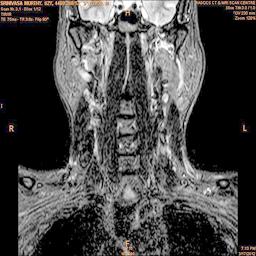

The developed algorithm presented in the previous section was coded using Matlab Version 8.0. The experiment was conducted by considering poor quality spinal cord images of having various lesions. The first column of Fig. 4 shows the axial view of neck spinal cord images of size pixels, respectively. The second column of Fig. 4 presents the same images enhanced using histogram equalization. As is evident from the results presented, the histogram equalization method performs global image enhancement operation which improves the contrast of an image but at the cost loss in image details. The third column of Fig. 4 shows the MSR based spinal cord image enhancement. It can be seen that from the result presented, MSR scheme improves the details that are not clearly visible in histogram equalization technique. In general, image enhancement achieved by MSR method is better compared to histogram equalization. However, the MSR method voilates gray world assumption. Therefore, the image enhanced by this scheme appears to be grayish. Although, numerous work have been reported for solving the problem due to gray world voilation, no work seems to developed for complete elimination.

The fourth column of Fig. 4 shows the image enhanced using Chao et al. []. It can be seen from the results presented that the reconstructed images of Chao’s method have black spots. The appearance of these dark patches degrades the visual quality of the enhanced image. The image enhanced using proposed multirate multiscale retinex image enhancement method presented in the fifth column of Fig. 4, overcomes the drawback of the Chao’s method. As we can see from the simulation results, image enhancement achieved by the proposed method has improved details with significant contrast enhancement. The enhanced images from the proposed method provides information to physicians, radiologists and researchers for various types of pathology detection.